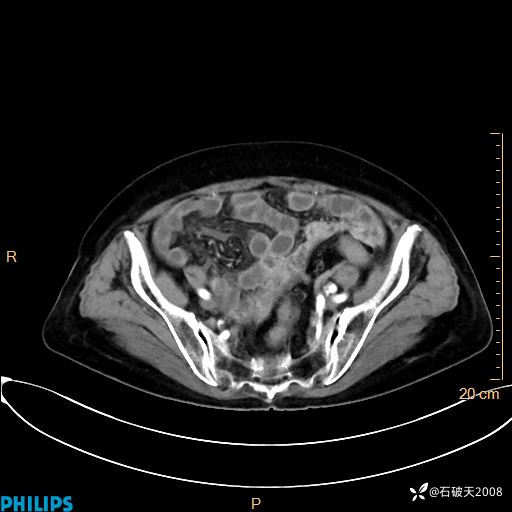

平扫